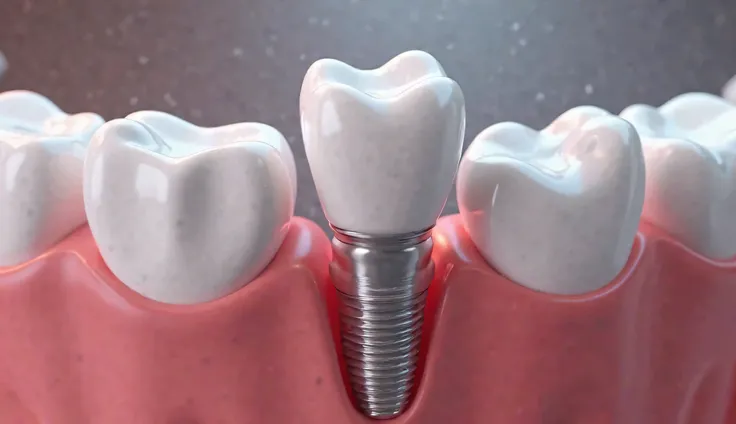

Create an artistic image that reimagines a dental implant as a luxurious work of art. The implant should be central in the composition, with intricate details that highlight its structure, such as the titanium post and the crown, all rendered in a refined and elegant manner. Surround the implant with artistic elements like flowing gold accents, delicate textures, and subtle patterns that evoke a sense of luxury and precision. The background can be minimalist, using soft gradients or abstract forms to keep the focus on the implant while enhancing the overall aesthetic. The image should blend the technical precision of a dental implant with the elegance and sophistication of fine art, creating a piece that is both visually striking and conceptually unique

Create an artistic image that reimagines a dental implant as a luxurious work of art

such as the titanium post and the crown